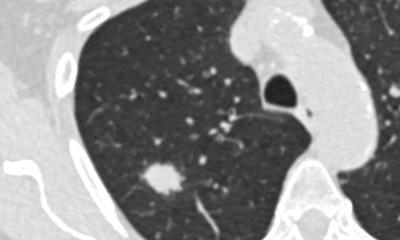

Doch Prof. Grenacher hatte die Fakten auf seiner Seite. Diverse Vergleichsstudien konnten nämlich nachweisen, dass die Multidetektor-CT aufgrund ihrer hohen Ortsauflösung (bis zu 0,33 Millimeter) mit der Endoskopie mindestens gleichauf liegt, wenn nicht sogar das überlegene Verfahren beim Tumorstaging ist. Die Datenlage der De-novo-Recherche überzeugte auch das Komitee. Seitdem ist das Verfahren in den 2011 verabschiedeten Leitlinien zum Magenkarzinom fest verankert.

Um die Strukturen im Submillimeterbereich optimal darzustellen, wird bei der Bildgebung des Abdomens ein spezielles Untersuchungsprotokoll gefahren, die sogenannte Hydro-CT, erklärt der Heidelberger Radiologe: „Dafür trinkt der Patient unmittelbar vor der Untersuchung einen bis anderthalb Liter Wasser. Für die Spasmolyse bekommt er zusätzlich noch Buscopan, damit die Magenperistaltik für 20 Minuten ausgeschaltet wird. Das getrunkene Wasser dehnt die Magenblase dann richtig schön auf, sodass wir die tumortragende Magenwand perfekt beurteilen können.“

Durch die hohe Auflösung lässt sich nicht nur zuverlässig beurteilen, in welchem Stadium sich der Tumor befindet und ob der Patient operabel ist oder nicht, auch Rezidive lassen sich frühzeitig aufspüren. Da die Uni- versitätsklinik Heidelberg auch Pankreas-Exzellenzzentrum ist, haben Prof. Grenacher und seine Kollegen hierzu eine Studie aufgesetzt, die aufzeigen konnte, dass diese Information einen signifikanten Überlebensvorteil für die Betroffenen bedeutet. Denn Pankreas- Patienten mit einem operierbaren Lokalrezidiv haben eine mediane Überlebenszeit von 26 Monaten, während Patienten mit einem nichtoperierbaren Lokalrezidiv im Durchschnitt elf Monate überleben.